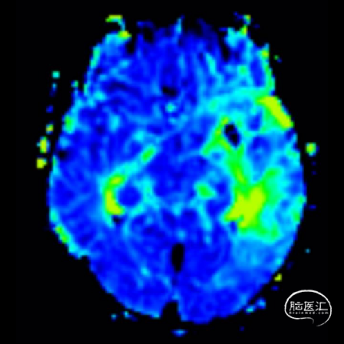

术后即刻影像。

支架植入后造影提示残余狭窄约10%。术中患者生命体征稳定,术后患者恢复良好出院,继续抗血小板聚集及他汀类药物治疗。